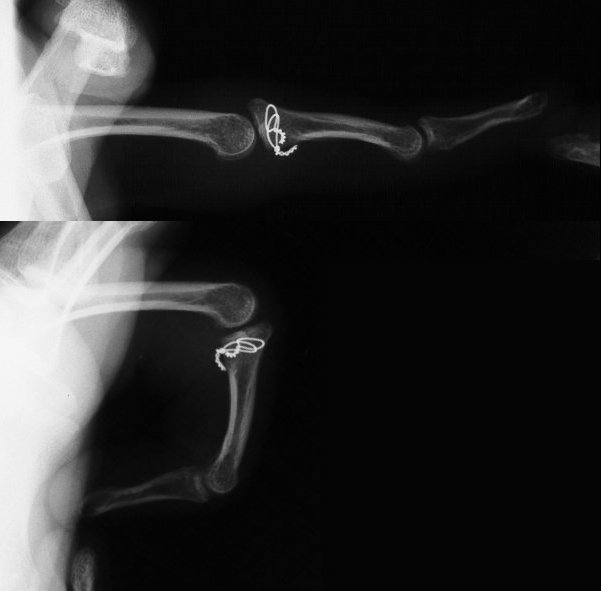

Xrays show an apparently healed PIP fracture dislocation with dorsal subluxation - but concentric tracking of the abnormal palmar articulation.

First impression was that the palmar fragment was probably big enough to take down and reinsert. However, comparison of films shortly after the fracture (above) and at two months (below) confirms the injury as a healed comminuted central impaction fracture with splay and hinging of the volar cortex.